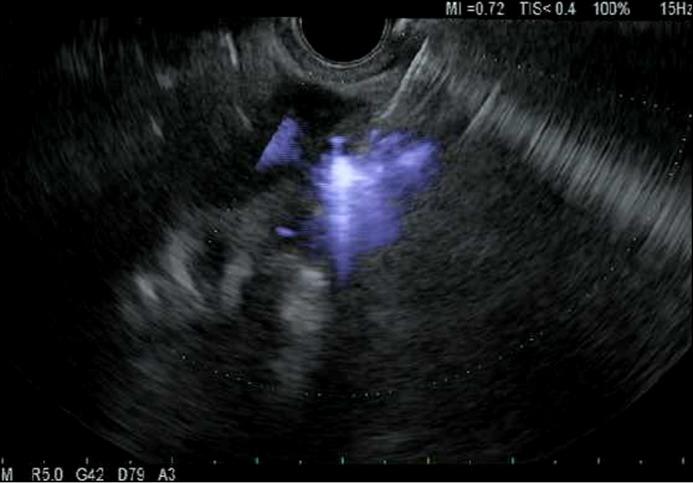

A 46-year-old female with no previous personal or family psychiatric history underwent endoscopic ultrasound (EUS)-guided celiac plexus blockade (CPB) to treat pain related to cystic fibrosis transmembrane conductance regulator-associated chronic pancreatitis. She had excellent response to her first three CPBs using bupivacaine and triamcinolone. The patient's subsequent CPBs were complicated by symptoms of racing thoughts, delusional thinking, and insomnia. She was diagnosed with acute psychosis secondary to triamcinolone. This is the first reported case of steroid-induced psychosis caused by EUS-guided CPB. Optimal treatment for steroid-induced psychiatric symptoms include dose reduction or discontinuation of steroids and administration of lithium, valproic acid, or atypical antipsychotics.

一名46岁女性,既往无个人或家族精神病史,接受了内镜超声(EUS)引导下的腹腔神经丛阻滞(CPB)以治疗与囊性纤维化跨膜传导调节因子相关的慢性胰腺炎引起的疼痛。她对前三剂使用布比卡因和曲安奈德的CPB反应良好。该患者随后的CPB出现了思维奔逸、妄想思维和失眠症状。她被诊断为曲安奈德继发的急性精神病。这是首例关于EUS引导下CPB导致类固醇诱导性精神病的报道病例。类固醇诱导性精神症状的最佳治疗方法包括减少或停用类固醇以及给予锂盐、丙戊酸或非典型抗精神病药物。